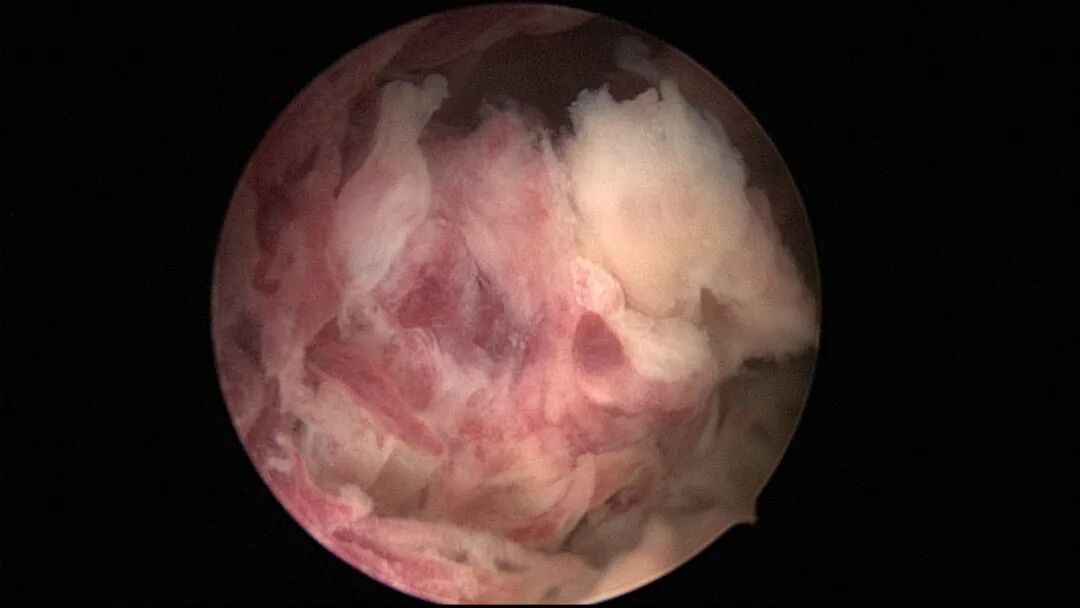

第五次宫腔镜:2023年8月初自然妊娠,药流不全,2023年8月底行宫腔镜清除残留胚物。宫腔下段前壁及左侧壁胚物残留,胚物与宫壁粘连,双侧输卵管开口可见,内膜稍苍白。单极电切环切除残留胚物组织,恢复宫腔形态,宫腔注入防粘剂,未放置球囊,患者拒绝送病检。